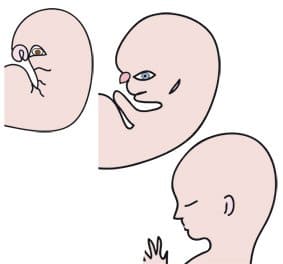

Il viso diventa più fine e si disegna. I tratti si modellano nel corso di questo mese e gli occhi, il naso, le orecchie e la bocca si posizionano. All’inizio, gli occhi sono situati praticamente sui lati della testa e, ...

Anche se il sesso del futuro bambino è determinato fin dal momento della fecondazione, non è evidenziabile prima del terzo mese di gestazione perché solo gli organi genitali interni sono in corso di sviluppo. Durante questo periodo maschi e femmine ...